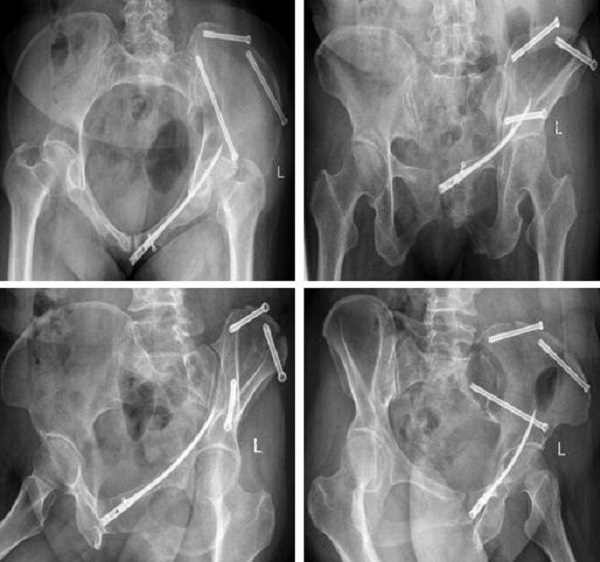

術(shù)后復(fù)查:

術(shù)前,創(chuàng)傷骨科郭永良主任醫(yī)師團隊?wèi)?yīng)用MIMICS軟件重建患者骨盆LC—II通道螺釘方向和長度,術(shù)中郭永良主任親自主刀,使用Schanz針協(xié)助閉合復(fù)位,結(jié)合術(shù)前模擬通道螺釘方向精確制導(dǎo),以最小的創(chuàng)傷將LC-Ⅱ通道螺釘順利置入合適位置,而且完美避開神經(jīng)及血管損傷,僅通過3枚螺釘使骨盆LC—II型骨折得到有效的穩(wěn)定固定。

近日,二一五醫(yī)院骨科醫(yī)院創(chuàng)傷骨科收治了一例54歲女性骨盆骨折患者,查體發(fā)現(xiàn)左髖關(guān)節(jié)因疼痛活動受限,骨盆擠壓分離試驗(+),X線及CT檢查提示骨盆骨折,骨盆骨折Young & Burgess 分型為LC—II型骨折,術(shù)前經(jīng)左下肢骨牽引,手法協(xié)助閉合復(fù)位拍片可見骨盆骨折復(fù)位良好,郭永良主任醫(yī)師詳細了解患者受傷機制,根據(jù)復(fù)位效果及骨折類型制定了微創(chuàng)化手術(shù)治療方案,即 LC-Ⅱ通道螺釘+恥骨髓內(nèi)針的微創(chuàng)化治療。